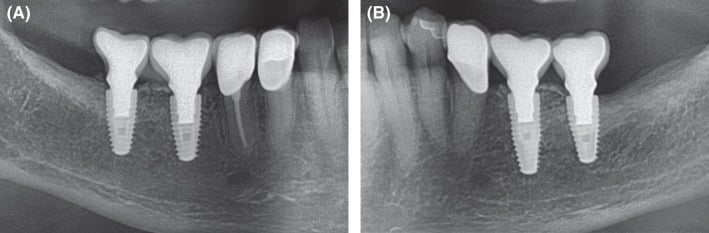

Figure 7.

Extracts from postoperative OPG after implantation and GBR in the third and fourth quadrant. A, fourth quadrant. B, third quadrant

Figure 10.

Extracts from postoperative OPG: Gingival former in the third and fourth quadrants in situ. A, Allogeneic site showing good integration of the implants and no loss of crestal bone. Relining layer of DBBM particles in situ. B, Same situation on the autologous site showing similar results compared to the allogeneic site